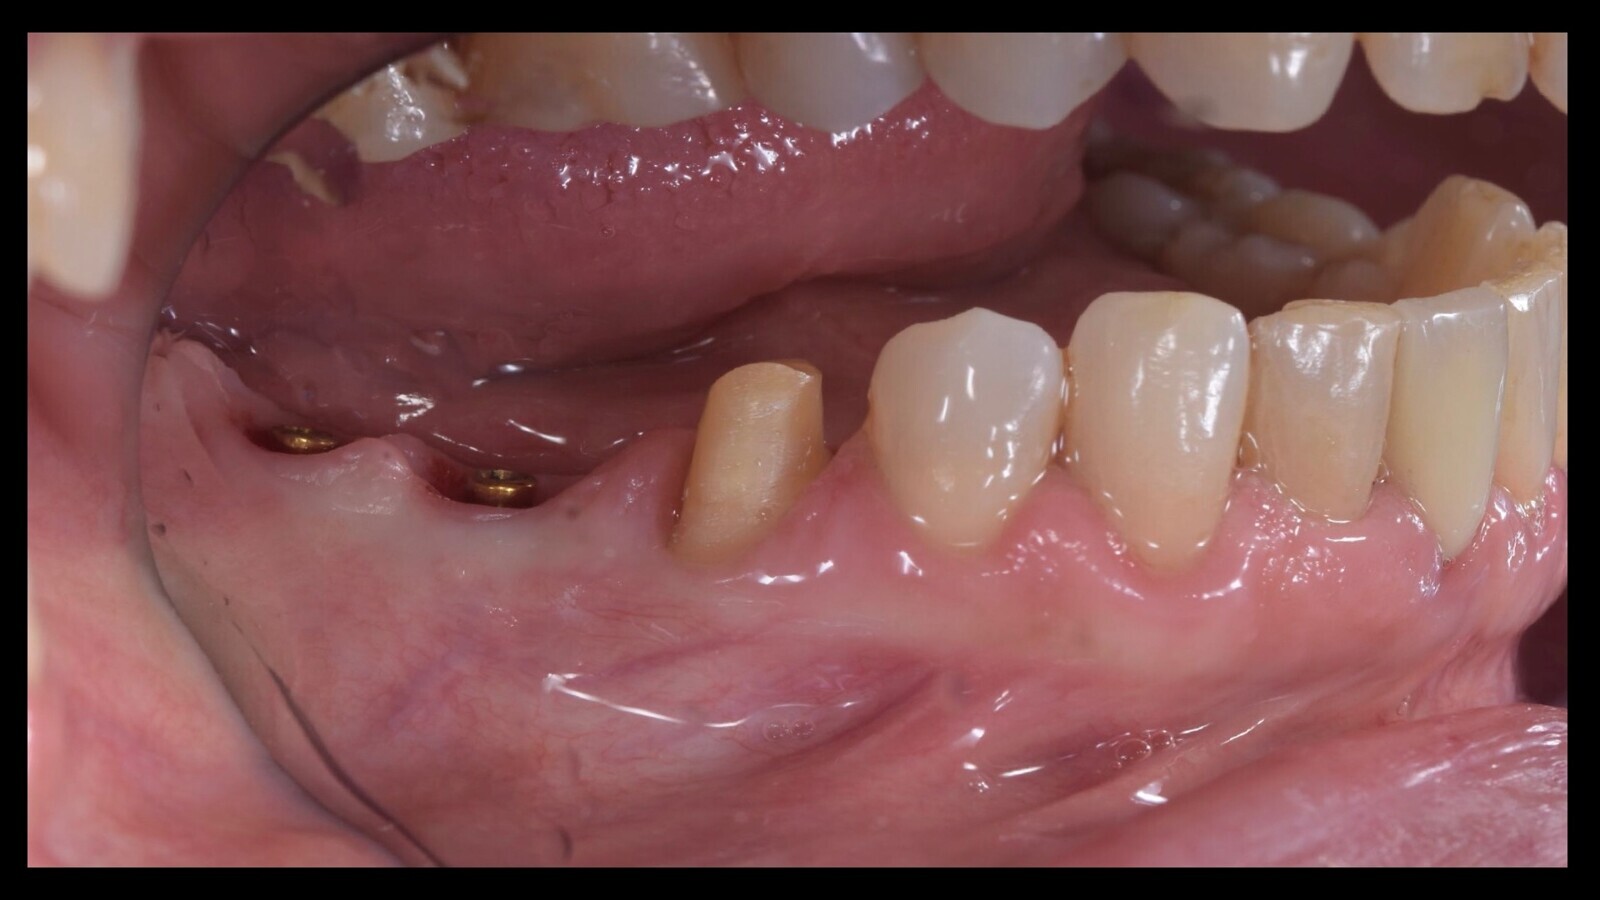

Figura 12. Durante la misma cita, se posicionaron los Equator con la técnica tradicional, como se observa en estas dos imágenes.

Figura 36. Esto permite el camuflaje del artefacto también gracias a las reducidas dimensiones del implante que, en la rehabilitación fija (a), permanece dentro del túnel mucoso (b).